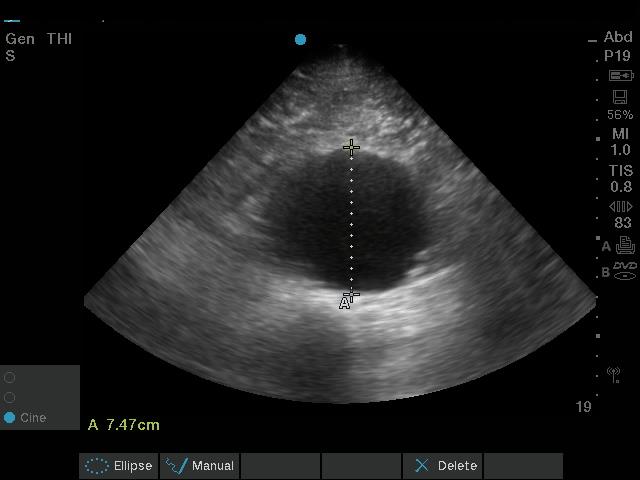

Transverse view of the abdominal aorta, below the renal arteries.

These images are consistent with an infra-renal abdominal aortic aneurysm (AAA), which is 7.47cm in diameter. The risk of AAA rupture is directly proportional to the diameter, with annual risk ranging between 1-10% for aneurysms that are less than 5cm in diameter (3). The annual risk of rupture with an aneurysm of this size is closer to 20%.